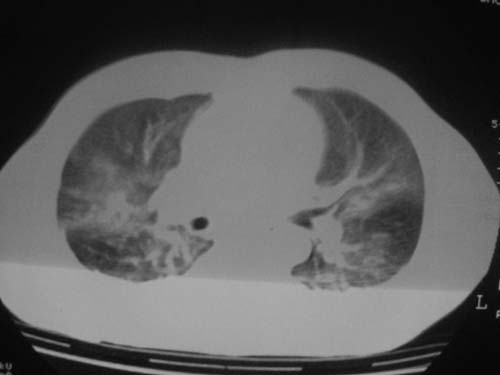

这是第三天拍的片子.